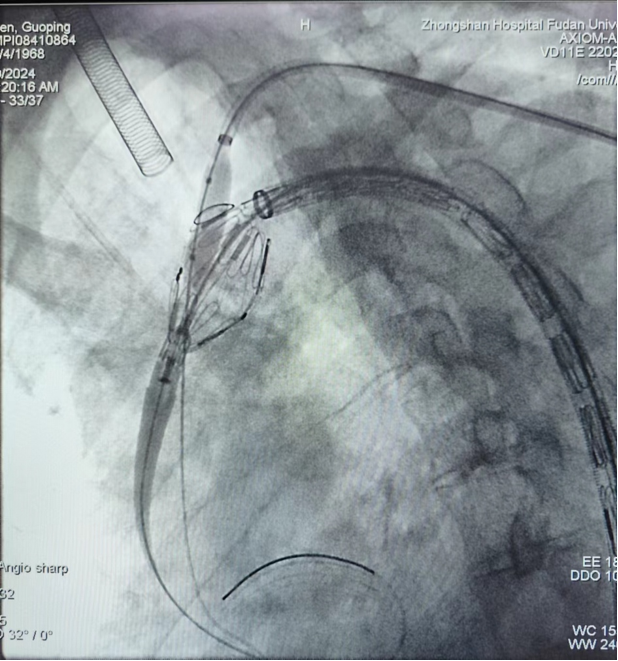

病例二(双开窗)

汪XX,男,52岁,主动脉夹层。LSA、LCCA双开窗。

术前

术中

术后